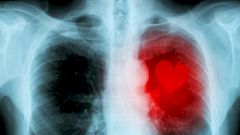

Аналогию можно продолжить. Подобно дорожным заторам, в сосудах тоже бывают самые настоящие пробки. Они возникают как следствие атеросклероза и чаще всего развиваются в течение долгих лет, а то и десятилетий. Худший (и порой окончательный) итог, к которому способна привести такая пробка, — классический инфаркт миокарда или внезапная смерть от паралича сердца.

Если жировые или известковые отложения накапливаются на стенках коронарных артерий (не блокируя их полностью, как при инфаркте), то они сужаются и теряют эластичность. Так продолжается до тех пор, пока сердечная мышца при нагрузке не начинает испытывать недостаток крови, насыщенной кислородом. Тогда возникает коронарная болезнь сердца, которая рано или поздно проявит себя тем или иным образом.

Частым следствием этого процесса становится стенокардия, или так называемая грудная жаба (Angina pectoris), которая обычно проявляется в виде приступов. Человеку неожиданно начинает казаться, будто кто-то положил ему на грудь ремень и сильно его затянул. Больному не хватает воздуха, и, разумеется, он может впасть в панику, ведь все указывает на инфаркт. Но вскоре боль и прочие симптомы отступают, и какое-то время все идет по-прежнему. Однако успокаиваться рано: подобные приступы стенокардии — очень тревожный сигнал, свидетельствующий о том, что коронарные сосуды значительно повреждены.